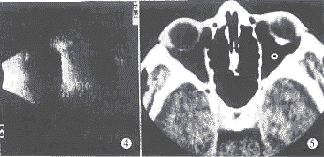

图1 脉络膜骨瘤眼底彩照 图2,3 脉络骨瘤FFA 图4 脉络膜骨瘤声像图 图5 脉络膜骨瘤CT扫描

B超探查(图4):后极部球壁强回声梭形物向玻璃体腔轻度突出,伴声影,增益降至周围组织回声消失,梭形光带仍可见。CT扫描(图5):左侧后部眼环卵圆形高密度钙化影,均质,CT值为+262 Hu,余处眼环及球内、眶内未见异常。诊断:左眼脉络膜骨瘤。病人拒绝激光治疗,现在观察中。